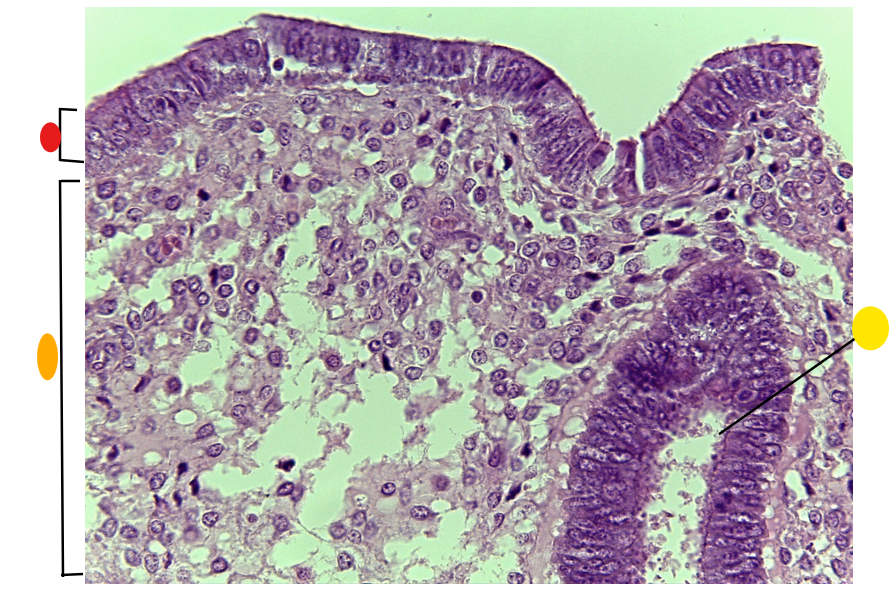

red

primordial follicles

red

primary follicles

red

tunica albuginea

orange

primary oocyte

yellow

primordial follicles

red

granulosa cells

orange

primary oocyte

what is this

primary follicle